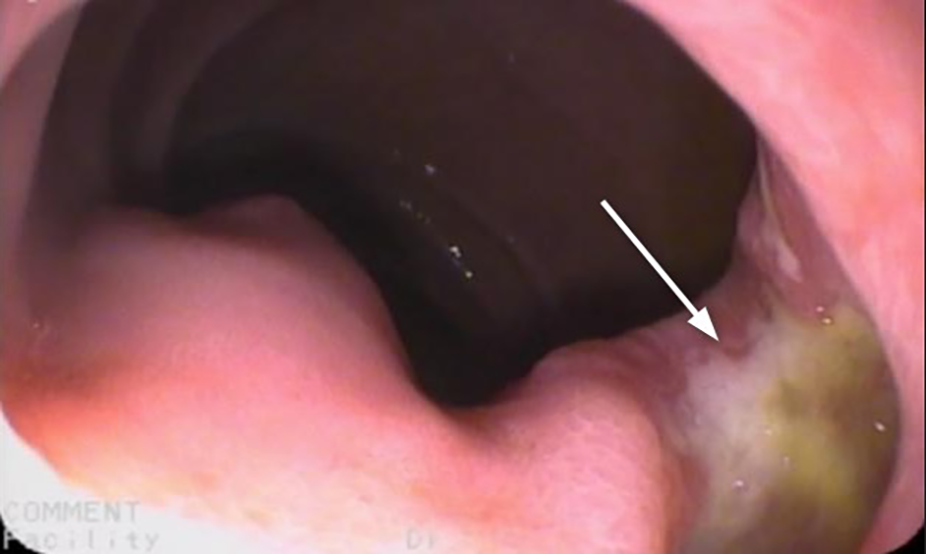

Esophagus-gastro-duodenoscopy (EGD) revealed a pale, mild trachealized esophagus with longitudinal furrows (Figure 1), normal gastric mucosa, and the presence of an edematous duodenal bulb associated with a tight stenosis of the descending duodenum (Figure 2); a neonatal endoscope was effective in overcoming the narrowing, and a post-stenotic juxta papillary ulceration was identified (Figure 3). Ileocolonoscopy was normal.

Figure 2. Duodenal stenosis (arrow): edema in the duodenum prevented the progression of the 9 mm endoscope. A 5 mm endoscope was used to overcome the stenotic tract.